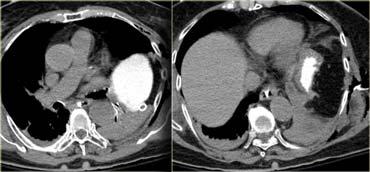

Trước tiên hãy quan sát các hình ảnh bên trái của bệnh nhân bị chấn thương gan.

Các dấu hiệu CT trong trường hợp này là gì?

Các dấu hiệu bao gồm:

- Mất tưới máu hoàn toàn thùy gan phải.

- Vùng ngấm thuốc cản quang (contrast blush) trong nhu mô gan, đồng thời lan ra ngoài bờ bên của gan.

- Tràn máu ổ bụng (Hemoperitoneum).

- Một vùng ngấm thuốc cản quang thứ hai ở mức thấp hơn.

- Tụ máu dưới bao gan lớn hơn 10 cm (tức là tổn thương độ 4)

- Vùng ngấm thuốc cản quang (contrast blush) (mũi tên)

- Không có tràn máu ổ bụng kèm theo

Vì vậy, mặc dù có thoát thuốc cản quang, bệnh nhân này sẽ được điều trị bảo tồn (không phẫu thuật) và có thể có tiên lượng tốt, do không có chảy máu vào khoang phúc mạc.

Thoát thuốc cản quang có ý nghĩa đặc biệt quan trọng, nhất là khi kết hợp với tràn máu ổ bụng.